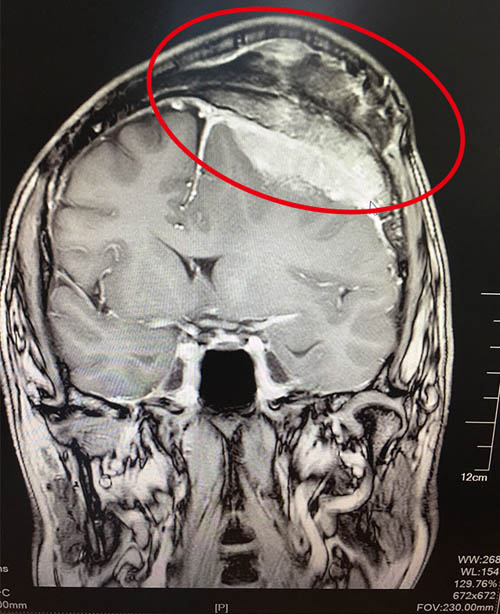

腦膜瘤(Meningiomas)是起源于腦膜及腦膜間隙的衍生物,發(fā)病率占顱內(nèi)腫瘤的19.2%,居第2位,發(fā)病高峰年齡在45歲左右,按照發(fā)病部位的不同,分為:矢狀竇旁和大腦鐮旁腦膜瘤,占總數(shù)1/4以上;大腦凸面腦膜瘤,占25%;嗅溝腦膜瘤和前顱底腦膜瘤,占8%-18%;鞍結(jié)節(jié)和鞍膈腦膜瘤,占4%-10%;蝶骨嵴腦膜瘤12%;顱中窩和鞍旁腦膜瘤6%;側(cè)腦室腦膜瘤4%-5%;顱后窩腦膜瘤14%,包括:小腦凸面腦膜瘤、小腦幕腦膜瘤、橋小腦角腦膜瘤、斜坡腦膜瘤、枕骨大孔腦膜瘤、第四腦室內(nèi)腦膜瘤。

許多人都知道腦膜瘤是很危險的疾病,它腦膜瘤起源于腦膜及腦膜間隙的衍生物,多數(shù)為良性腫瘤,發(fā)病率位居顱內(nèi)腫瘤第二位。腦膜瘤...【詳細】